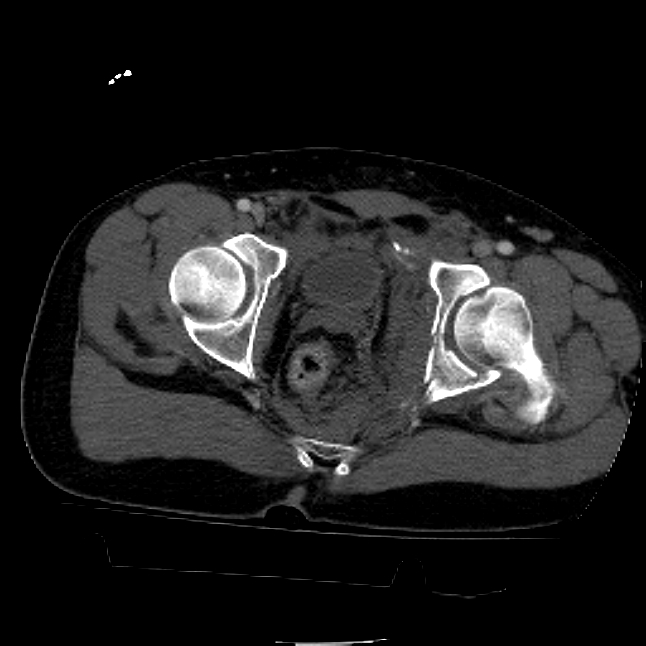

25 yo brittle diabetic, became hypoglycemic and passed out on his motorcycle. Sustained bilateral lateral Hoffa fractures with associated LCL injury on the right and right distal radius fracture. I have questions regarding his pelvic ring/acetabular fracture on the left. Appears to be a very low posterior column fracture with associated posterior wall, marginal impaction. Superior and inferior rami fractures as well on the left giving him a floating segment of inf ramus/ischium/posterior column, but no detectable posterior ring injury. Should the posterior column/posterior wall fracture be addressed surgically because of the marginal impaction? Or is this fracture low enough to be treated non-operatively? I appreciate the input.

It's an interesting case. The plain films show the impaction, but most of the joint looks pretty good. The CT cuts look awful, though.

The impaction is so big I don't think I would ignore it. It IS down low, but it takes up almost the whole southern hemisphere of his joint.